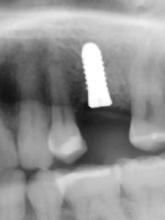

A pótlásra szoruló fogat, vagy fogakat minden esetben legalább egy évvel a fogpótlást megelőzően eltávolítottuk. Ezen esetek egyikében sem végeztünk alveolus vagy állcsontgerinc prezervációt az eltávolítás során, illetve minden páciens jó szájhigiéniával rendelkezett. Egy kivételével minden páciensnél radiológiai analízist végeztünk CBCT-vel,

digitális implantátumtervezés követett (SICAT és Sidexis, mindkettő Dentsply Sirona; 1. ábra).

Mind a hat implantátum esetén kétlépcsős műtétet végeztünk. Minden sebészeti eljárást bódítás, illetve preoperatív szisztémás antibiotikus terápia nélkül végeztünk. A négy eset közül kettőnél leukocitában és vérlemezkében gazdag fibrint (L-PRF) alkalmaztunk a beavatkozás során (IntraSpin, BioHorizons; 2. táblázat). Minden esetben a pontos CERALOG menetvágási (maximum 15 ford./perc) és fúrási (maximális fúrási fordulatszám: 550–800 ford./perc) protokollt követtük. Az összes implantátumot manuálisan helyeztük be 35 Ncm maximális nyomatékkal. Az implantátumokba PEEK zárócsavar került (2. ábra). A lágyszövetet atraumatikus, felszívódó varrattal, szorosan zártuk/összevarrtuk. A műtétek után szövődmények nem jelentkeztek. A pácienseket arra kértük, hogy a műtét utáni héten naponta kétszer öblögessenek klórhexidinnel (PERIO-AID, 0,05%, DENTAID). Az alsó állcsontnál három hónapos, a felső állcsontnál öt hónapos gyógyulási időt vettünk figyelembe. Három hónap (1. eset) és öt hónap (2., 3. és 4. eset) elteltével a műtétek második stádiumát helyi érzéstelenítés mellett végeztük. A gyógyu-

lási csavarokat (PEEK titáncsavarral) maximum 15 Ncm-rel húztuk meg (3–6. ábra). Az összes implantátum kiváló stabilitást mutatott (a mérésekhez Periotestet használtunk, a Medizintechnik Gulden jóvoltából), és teljesen osszeointegrálódott. Ezt a radiológiai vizsgálatok is megerősítették.

2a 3a 4a 2b 3b 4b 2c 2d Pozíció Implantátum átmérő Implantátum hossz L-PRF Behelyezési nyomaték Eset 1 #35 4 mm 12 mm Nem 35 Ncm Eset 2 #25 4 mm 12 mm Nem 30 Ncm #26 4 mm 8 mm Nem 25 Ncm Eset 3 #16 4 mm 8 mm Igen 25 Ncm #26 4 mm 10 mm Igen 30 Ncm Eset 4 #26 4 mm 10 mm Igen 30 Ncm

2. a–d ábra: PEEK zárócsavarok az implantátumokba helyezve, 1. eset (a). 2. eset (b). 3. eset (c), 4. eset (d). 3. a–b ábra: Röntgenfelvételek három hónap után (a) és a gyógyulási csavarok behelyezve (b, 1. eset). 4. a–b ábra: Röntgenfelvételek öt hónappal később (a) és a gyógyulási csavarok behelyezve (b, 2. eset). 2. táblázat: Az implantátum tulajdonságai.

tottuk (az okklúziós koncepciók alapján az implantációs pótlások nem voltak vezető fogak, és csak könnyű érintkezéseket alakítottunk ki, amelyeket artikulációs papírral ellenőriztünk). A páciensek instrukciókat kaptak a megfelelő szájhigiénére vonatkozóan, összpontosítva a fogköz kefékkel történő tisztítására. Végső kontroll röntgenfelvétel készült. A PEEK felépítmény nem radioopák, így az implantátum és a korona közötti távolság könnyen meghatározható a röntgenfelvételen: a felépítmény megfelelően illeszkedik az implantátumban, ha az implantátum válla és a korona alsó széle közötti rés 0,55 mm a röntgenfelvételen (8–11. ábra)